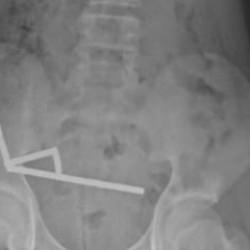

GÜNCEL4 YIL ÖNCEKüçük Uras'ın karın ağrısının nedeni herkesi şaşırttı! Bağırsağından 19 tane çıktıİstanbul'da yaşayan 4.5 yaşındaki Uras Aslan Aktaş, şiddetli karın ağrısı şikayetiyle ailesi tarafından hastaneye götürüldü. Çekilen röntgen filmi sonucu küçük çocuğun bağırsağında tam 19 tane 'neodyum mıknatıs' tespit edildi. Çocuk Cerrahisi Uzmanı Prof. Dr. Ali Çay tarafından ameliyata alınan Aktaş, sağlığına kavuştu. -